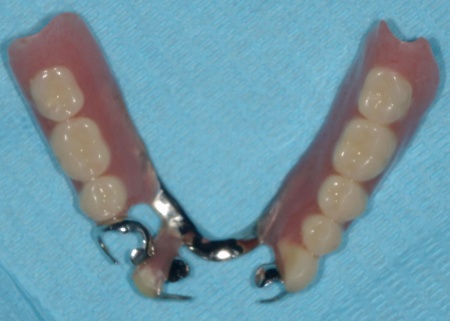

また、下顎は保険診療の部分入れ歯を再作製し、上下の噛み合わせの回復を図りました。

最後に、完成した入れ歯を装着し、噛み合わせや使用感に問題がないことを確認して、治療を終了しています。